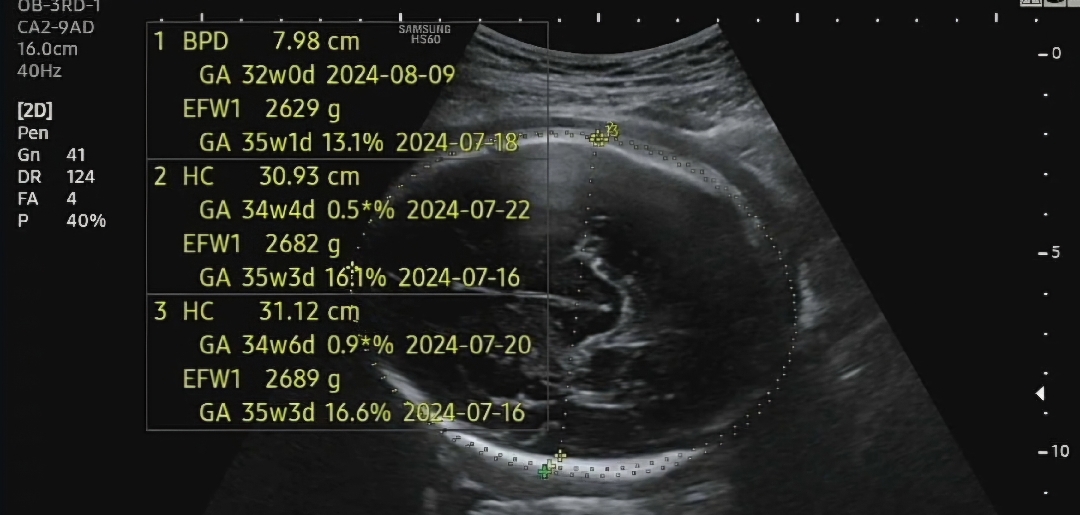

37주 2일차에 검사했는데 쌤이 쥐어짜내며 재검에 재검을 3번을 해서 크게 잰게 35주래요.. 심지어 머리직경은 32주인거 보이시죠ㅜㅜ? 열달후에로 보니 평균의 1cm 가량의 차이가 날 정도로 머리둘레랑 머리직경만 유독 작아요.. 머리가 작아서 제왕 잡은 상황인데 베동 글 중에 35주 아기 뇌 무게가 39-40주 애기의 뇌의 2/3뿐이란 글을 보니 기분이 싱숭생숭해요... 최대한 품어서 놓고 싶은데 의사쌤은 이렇게 안자라고 있으면 놓아서 키워야한다는데 뭐가 맞는지 모르겠어요... 맘님들은 이런 상황이면 어떻게 하실거 같은지 알고싶어요 1. 뱃속에 더 품어서 낳기 2. 의사쌤 말대로 낳고 키우기